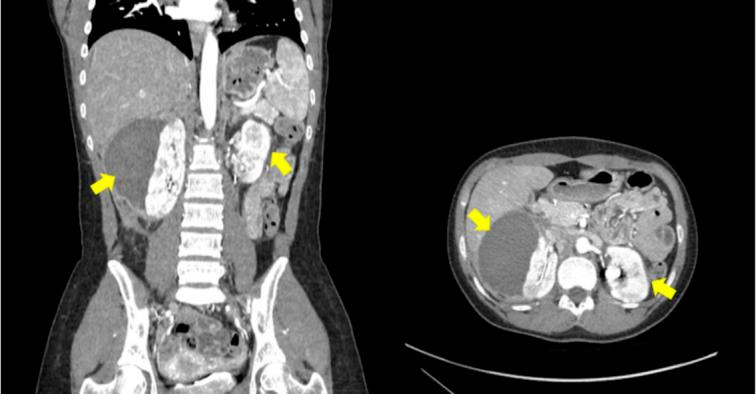

An 18-year-old female presented with right flank pain, fever, and a history of joint pain, Raynaud's phenomenon, livedo-like rash, and chronic abdominal pain. Physical examination revealed subcapsular hematoma in the right kidney. Further evaluation showed positive serologic tests for rheumatoid factor and antinuclear antibody (ANA). Genetic testing confirmed DADA2 homozygosity. The patient was discharged on the appropriate medications.

一名18岁女性出现右侧胁腹疼痛、发热,并有关节疼痛、雷诺现象、类网状青斑皮疹和慢性腹痛病史。体格检查发现右肾包膜下血肿。进一步评估显示类风湿因子和抗核抗体(ANA)血清学检测呈阳性。基因检测证实为DADA2纯合子。患者出院时服用了适当的药物。

本病例报告突出了ADA2缺乏症的多种临床表现,特别关注双侧肾包膜下血肿。这一发现强调了在出现不明原因肾脏表现的患者中考虑DADA2作为鉴别诊断的重要性。提高对DADA2各种临床表现的认识将有助于受这种罕见遗传病影响的患者早期诊断、适当管理并改善预后。